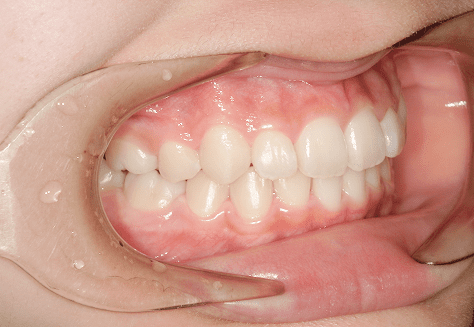

S.K

治療前

治療後

主訴

歯が重なっていて気になる。前歯が出ていて唇が閉じにくい。ハミガキがしにくい。

診断

上顎前突・叢生

年齢/性別

20代/男性

抜歯部位

上下第三大臼歯

使用装置

上下インビザライン

保定装置

上下ビベラリテーナー

料金

初回資料採得・・・・・・・30,000円

診断料・・・・・・・・・・33,000円

動的治療終了時資料採得・・5,500円 -

基本料金

990,000円

診察料金

1,100円×33回

治療期間

3年5カ月